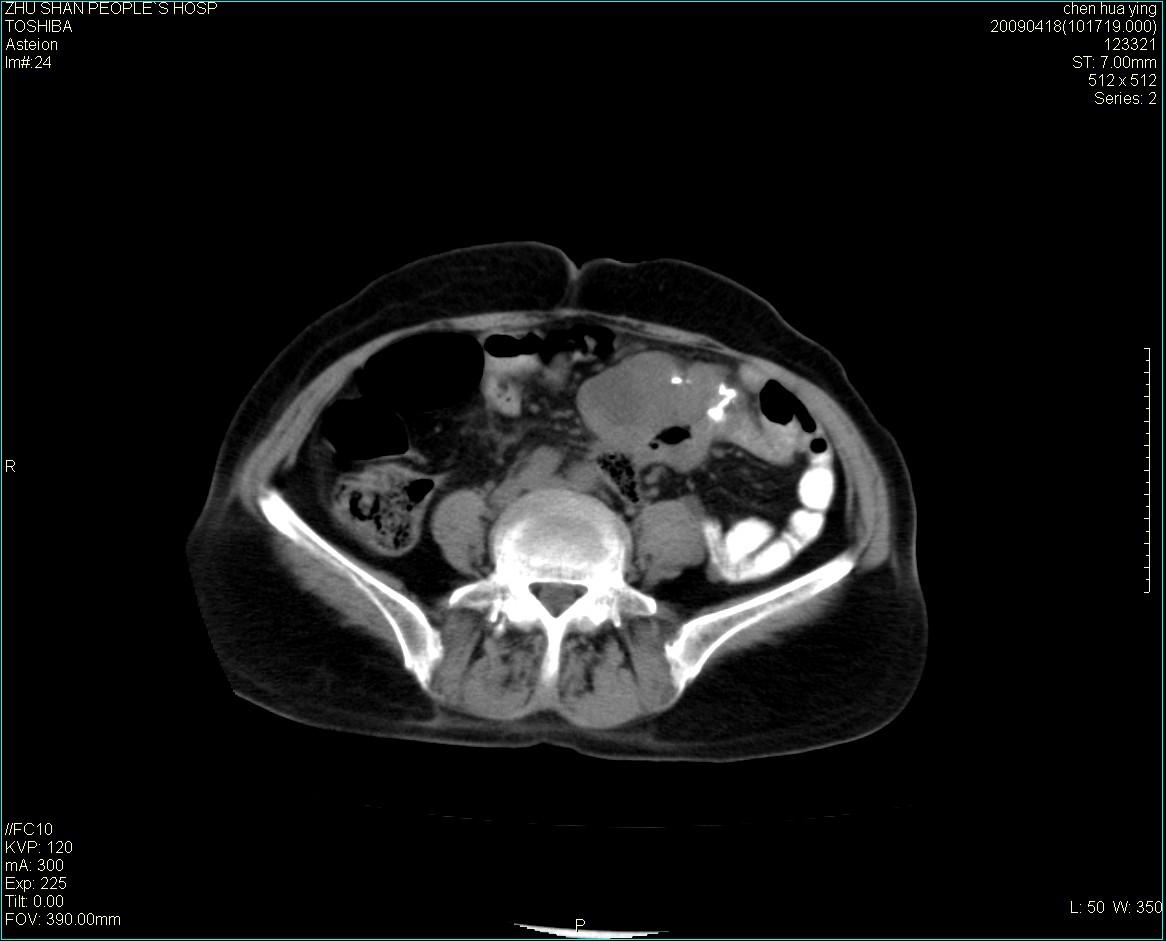

女性病人 65岁 腹部包块半年余结肠造影未见异常.

病灶略呈圆形有分叶状,上部层面呈实性,右侧见圆形低密度区,灶内见团块状钙化,病灶下方与肠管分境不清,考虑间质瘤可能性大,建议肠道准备后增强